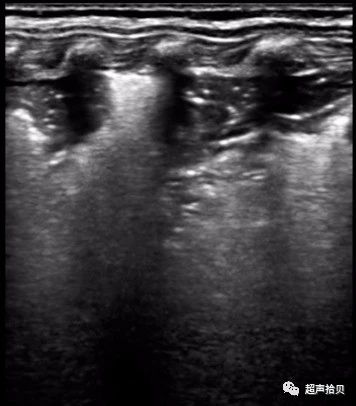

图4肺部超声检查发现新生儿肺炎(胎龄38周,体重4000克),入院时患有呼吸窘迫症状和3天发热史。 根据胸部听诊时密集的湿啰音,常规血液检查结果和胸部X线检查结果诊断该患者肺炎。 肺部超声显示两个大面积的肺实变,边缘不规则,不均质回声,胸膜线和A线消失